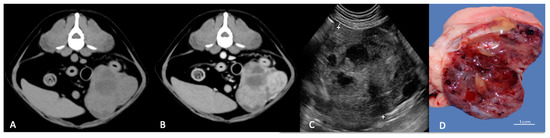

Imaging of Prostatic Neoplasia